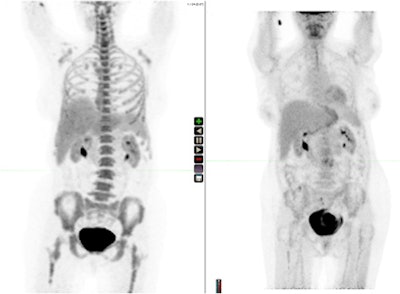

A fluoro-L-thymidine scan (left) and a fluorodeoxyglucose PET scan (right) of the same patient. Images courtesy of Dr. Peter Choyke."It's very useful since it can detect metastatic disease earlier and may replace conventional bone scans in the near future for many indications," said Choyke, adding that in many respects sodium fluoride is a "dumb" agent because it simply reflects bone metabolism and is not a molecularly targeted agent.

FLT is more highly targeted and reflects cell proliferation. Since inflammatory masses are not highly proliferative, FLT scans can be used to distinguish between tumors and inflammatory masses in treated patients in which the FDG scan is positive, he remarked.